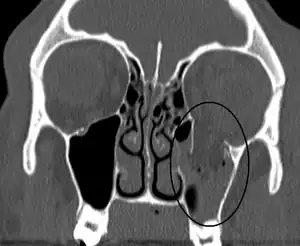

| An orbital blowout fracture of the floor of the left orbit. | |